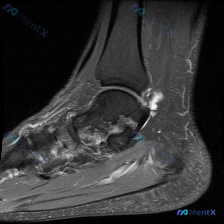

本病例提供了膝关节MRI T1序列轴位髌股关节层面影像,临床提示存在软骨异常,要求读片分析。

本次扫描层面为髌股关节层面,影像可见:

- 髌骨、股骨髁关节软骨:髌骨后方软骨连续光滑,股骨滑车软骨厚度均匀,均未见明确局灶性缺失、信号不均匀或不连续

- 髌股关节间隙:对位关系良好,无脱位/半脱位,未见明显关节积液

- 骨骼结构:髌骨、股骨髁骨髓信号均匀,骨皮质光滑,无骨质破坏、骨皮质中断或明显骨髓水肿

- 周围软组织:髌周皮下脂肪信号均匀,无异常肿块或渗出

- 补充说明:本层面未显示完整半月板,仅可见部分肌腱附着,走行自然无明显异常

影像初步结论:当前T1轴位切面未见明确形态结构异常、软骨缺损或明显骨髓信号改变